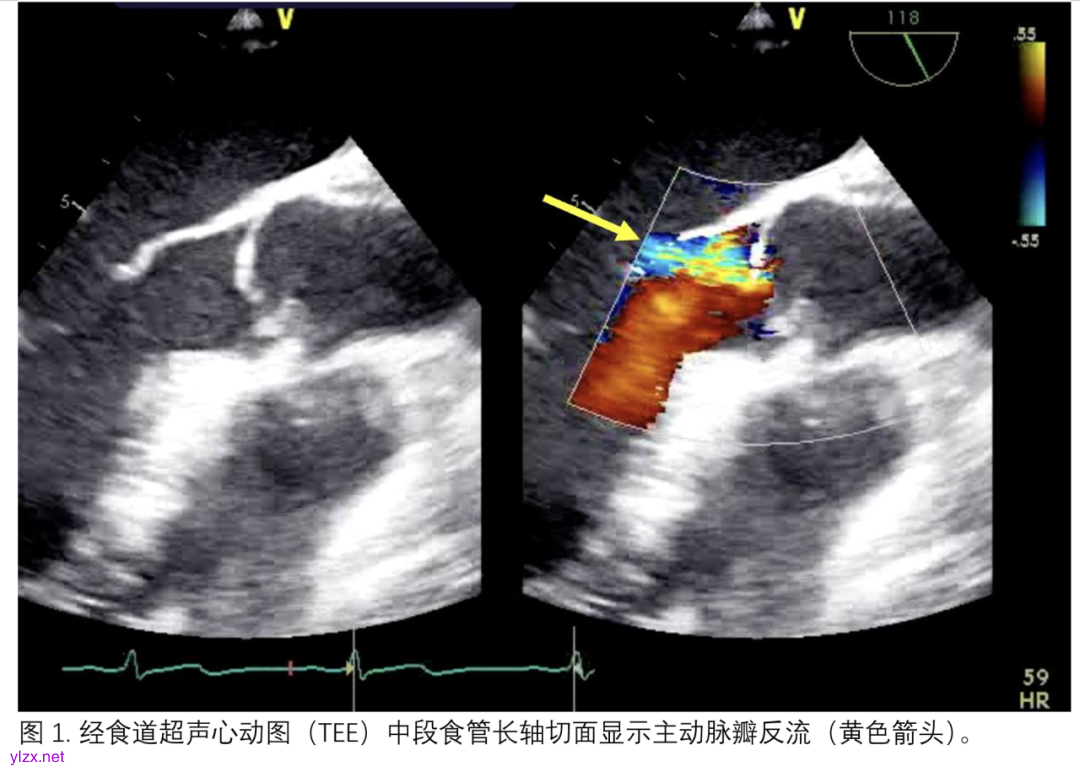

了解心室大小、壁厚和局部壁异常可以帮助指导管理和治疗。显著的主动脉瓣关闭不全会导致肺水肿和左心室扩张,从而导致壁应力增加、氧耗增加,容易在已经脆弱的左心室中引起缺血。在任何插管之前评估主动脉夹层很重要,因为其存在是V-A ECMO的禁忌症(图1)。